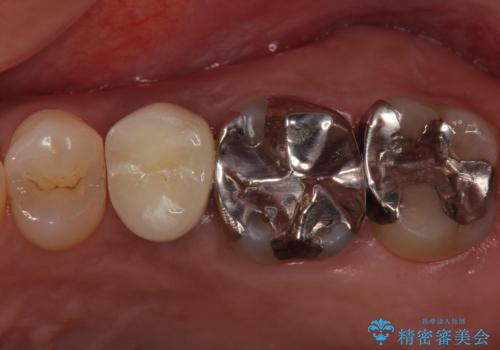

歯茎が腫れる インプラントでの治療

- 40代女性

- 10ヶ月

- 5-10回

- 左上5/インプラント:242,000円 骨増生:55,000円 カスタムアバットメント:110,000円 インプラント用仮歯:22,000円 ジルコニアクラウン:121,000円 合計550,000円費用は治療当時の料金となります